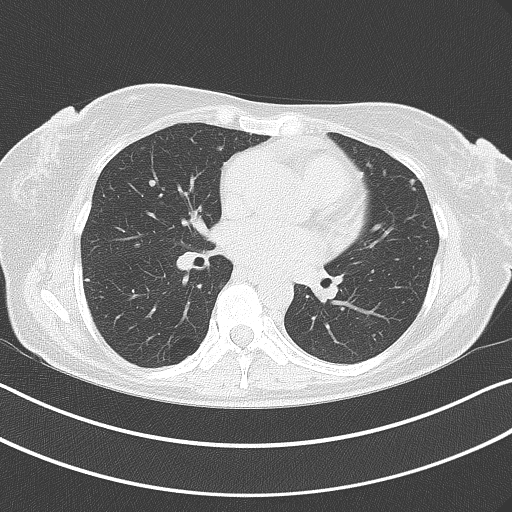

Image Grid

4×3 grid: Rows show different image types (Original NATIVE, Reconstructed NATIVE, Original VENOUS, Generated VENOUS), Columns show windowing techniques (No Window, Lung Window, Mediastinum Window)

Reconstructed NATIVE CT scan (cycle consistency)

No window - Raw intensity values

Reconstructed NATIVE CT scan (cycle consistency)

Lung window (WL -600, WW 1500 → Low −1350, High +150)